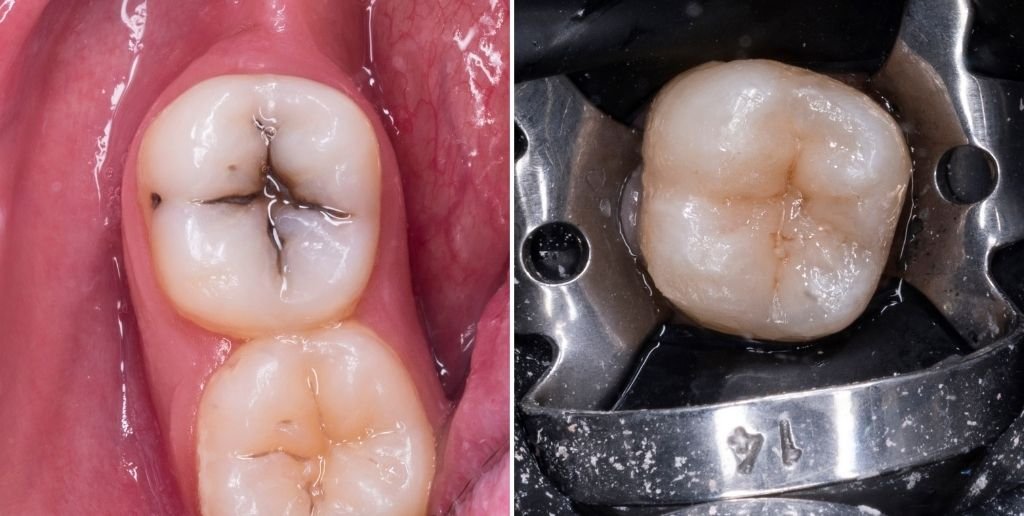

Restaurações em cerâmica em dentes posteriores

Como os nossos dentes molares são uma parte essencial para o processo de mastigação, a resistência do material utilizado nas restaurações é essencial para um resultado funcional e confortável para o paciente.

Por causa disso, as nossas restaurações são realizadas com cerâmica, pois é provado este ser o melhor material para realizar restaurações nos dentes molares, hoje em dia.

Casos Clínicos

Veja alguns dos nossos casos de sucesso neste tratamento, e as transformações que conseguimos realizar para o ajudar a atingir os seus resultados desejados.